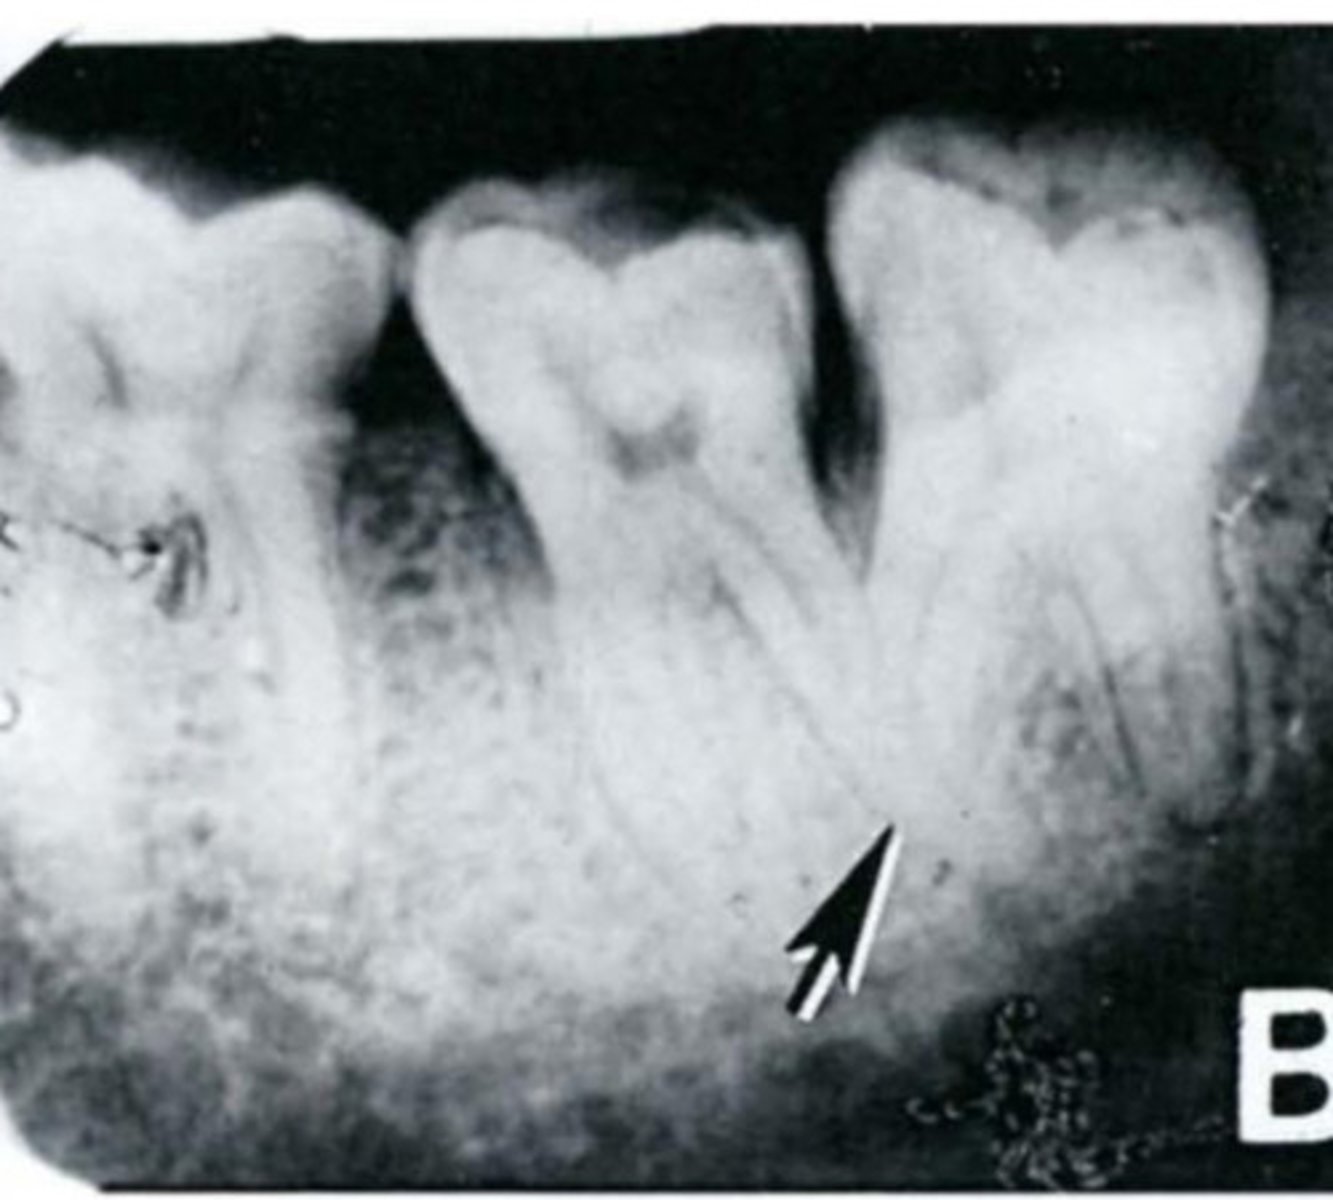

What is sequestration in chronic osteomyelitis?

Necrotic bony islands